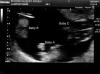

Она ждала ребенка, но УЗИ показало то, чего никто не ожидал…

Выяснилось, Карен ошиблась и насчет количества детей, и насчет болей. Как оказалось, ждали молодые мама и папа аж целую тройню, а боли были из-за того, что малыши боролись за место в животе мамы. Это невероятно, но три близнеца были однояйцевыми, что встречается чрезвычайно редко (1 шанс к 200 миллионам).